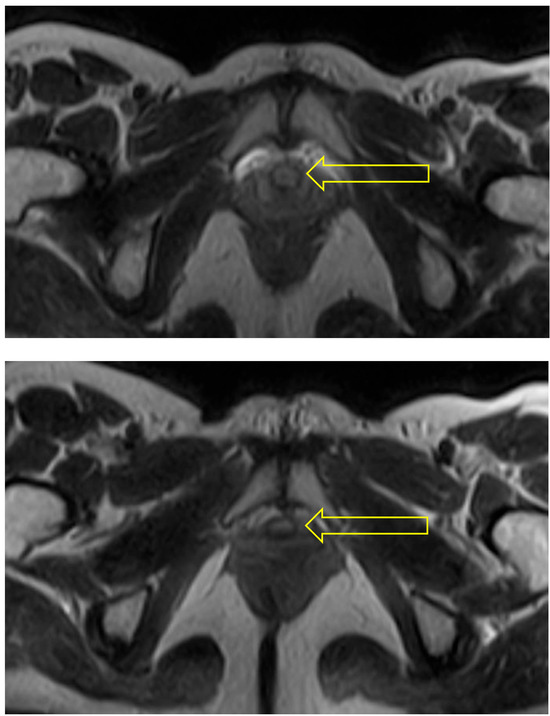

In the supine bridge pose (Setu Bandha Sarvangasana), the axial images show an oval shape of the urethra beginning just below the bladder neck which continues to be evident at the mid-urethra (see Figure 5). In addition, narrowing was evident in the mid-urethra in sagittal scans (see Figure 6); when measurements were compared to supine baseline images where the mid-urethra measured 12 mm, the supine bridge pose measurement was 8 mm. Comparison with standing posture images also suggested an increase in urethral length during the supine bridge pose, with a change from a baseline of 36 mm to 45 mm (Figure 7).

Figure 5. Supine bridge pose: These axial images show an oval shape of the urethra (indicated by arrow) beginning just below the bladder neck (upper) and continuing to be evident at the mid-urethra (lower). The mid-urethra is known to have a smaller diameter than the distal urethra. The area of hyperintensity around the urethra in comparison with resting state images may indicate pooling of venous blood due to activity within the pelvic floor musculature generated when holding this pose.

Figure 6. Supine bridge pose: This sagittal scan illustrates a view where the entirety of the course of the urethra can be visualized, and a narrowing is evident at the mid-urethra (lower arrow). The bladder neck is identified by the upper arrow and did not change in diameter or volume from supine to bridge pose.

Figure 7. Supine scan: This resting supine scan provides comparison with the supine bridge pose scan shown in Figure 6. In supine imaging the anatomic outline of the urethra (indicated by arrow) shows no regional narrowing.